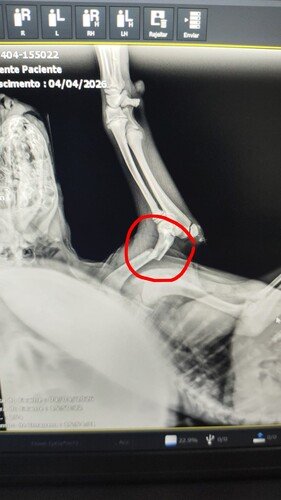

Ele resistiu à força do impacto, mas agora luta contra algo silencioso e cruel: a dor de uma fratura que o impede de caminhar e a fraqueza de um corpinho que ainda está em desenvolvimento. Por estar no início de um quadro de desnutrição, precisamos agir agora para que ele ganhe peso e tenha forças para enfrentar a cirurgia.